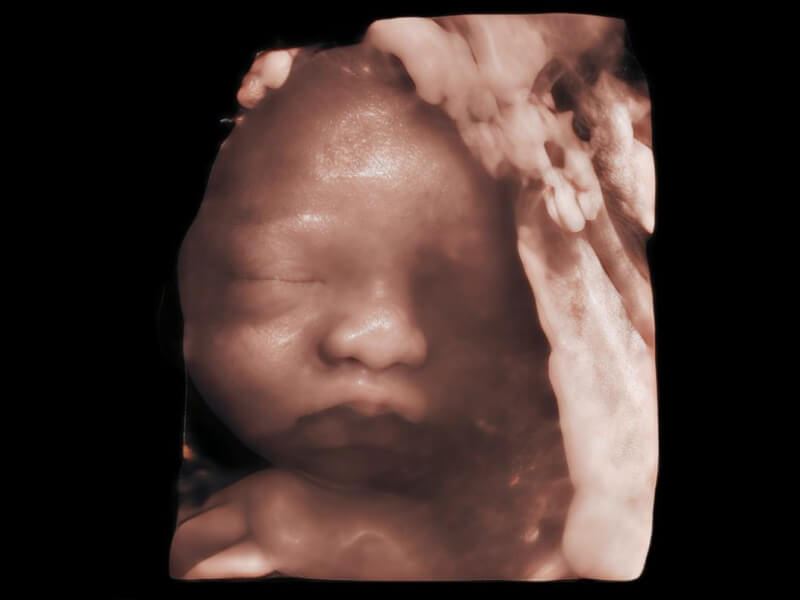

作为开立医疗全新打造的超高端旗舰超声产品,从探头抬起唤醒开启扫查到多维探头发射接收,通过先进的场成像发射、自适应聚合重建等技术,基于RF Data原始射频数据在图像生成、高端功能等方面实现突破,为妇产科、儿科提供全方位临床解决方案。

梦溪®P80以“关爱女性”为基石,提供全方位的解决方案,量身定制以满足女性的健康需求,涵盖妇科、生殖健康检查、产前筛查及产后康复等领域。